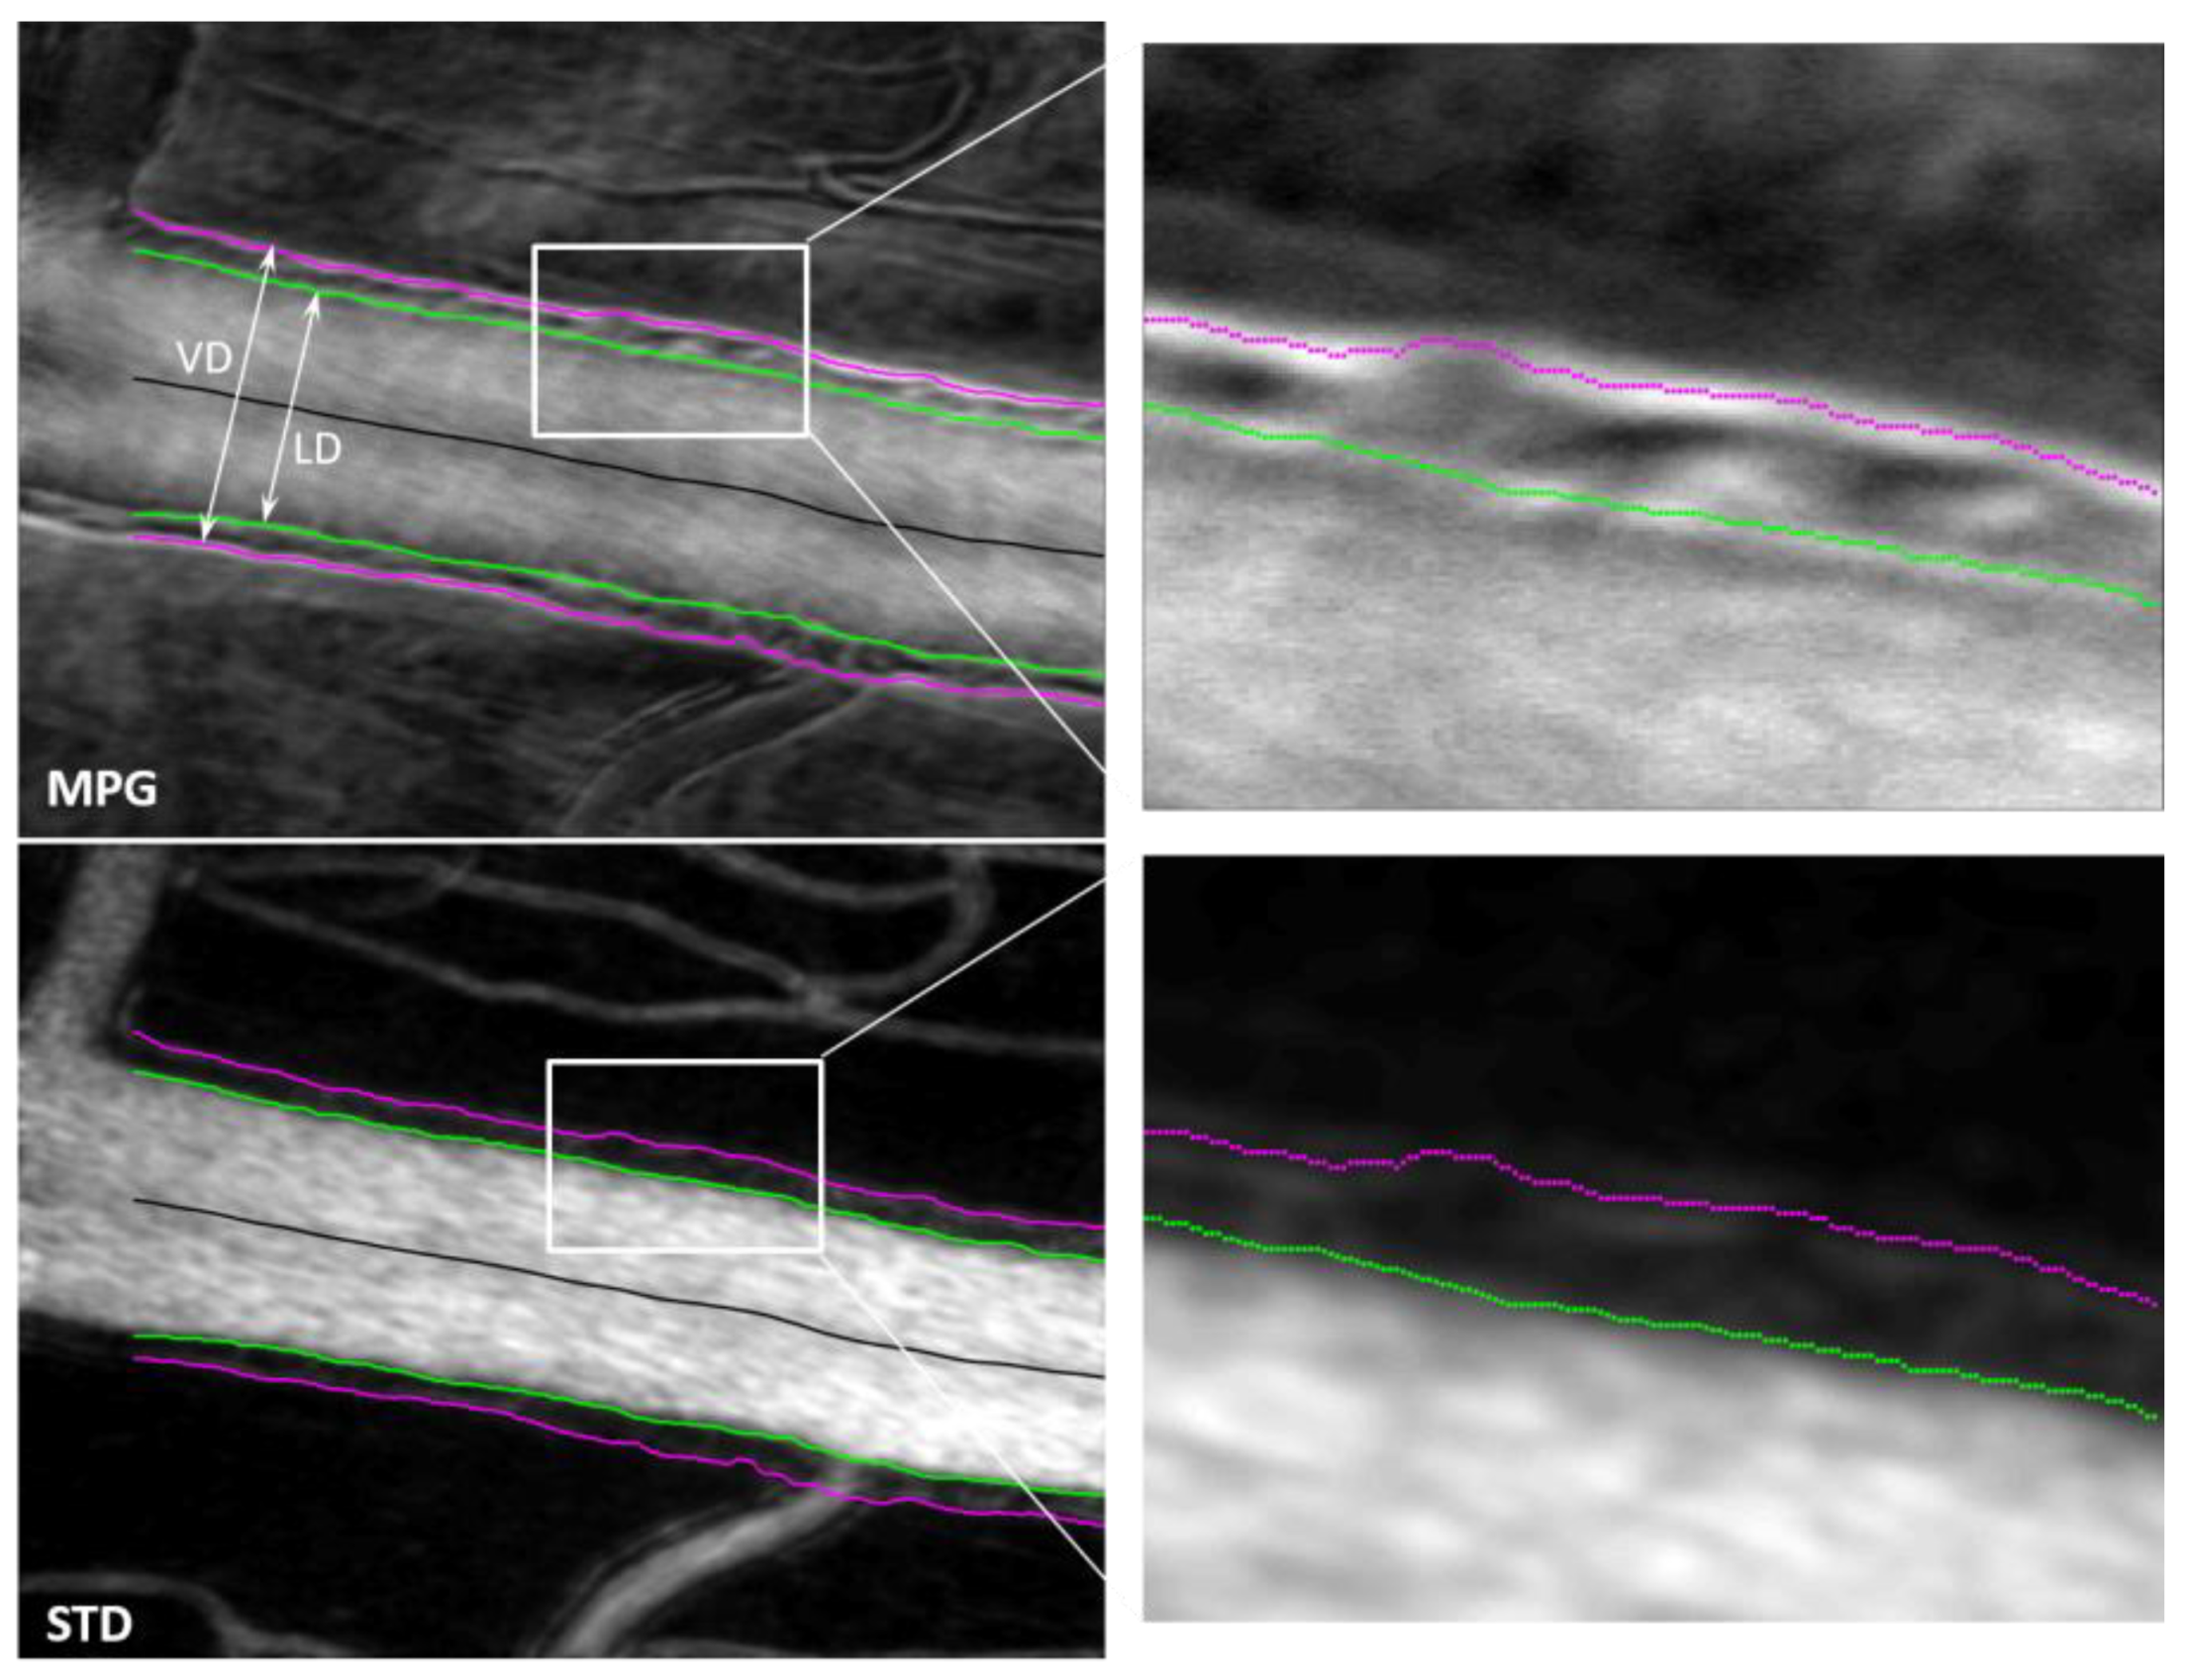

Two orthogonal split-detector images are used to calculate the magnitude of the phase gradient, which highlights local variations in the refractive index. The gradient maxima indicate the location of structural changes (edges) associated with the blood vessel wall boundaries. STD images highlight the blood flow through motion contrast, and the edges of the flow shown in these images correspond to the lumen boundaries. Segmentation of the gradient maxima and of the STD images provides the inside and outside boundaries of the vessel walls, as illustrated in Figure 4, and enables calculation of the wall-to-lumen ratio (WLR) and of other structural characteristics of the retinal vasculature.

Figure 4.

MPG (top) and STD (bottom) images with segmented vessel walls (magenta and green). The right-side column shows a magnified view of the white rectangle area in the left-side images. (VD—vessel diameter; LD—lumen diameter).

Various retinal structures have a different refractive index than the tissue surrounding them. Minute variations with respect to the surroundings generate little contrast and render the structures basically transparent in transmission or hard to see in reflection. Phase imaging is sensitive to such small refractive index variations and provides additional contrast to image such structures, sometimes called phase objects. Phase gradients can be used to identify the borders of phase objects, which represent the location where the refractive index has the largest jump. Quad imaging, as presented here with two orthogonal split detection directions, can be used to calculate MPG, which highlights local variations in the refractive index. The gradient maxima indicate the location of the structural changes (edges) associated with the blood vessel wall boundaries, as shown in Figure 4. STD images highlight the blood flow through motion contrast and the edges of the flow shown in these images correspond to the lumen boundaries. Segmentation of the gradient maxima and of the STD images provides the inside (green in Figure 4 and Figure 5) and outside (magenta) boundaries of the vessel walls and enables the calculation of VD, LD, WLR, and of other structural characteristics of the retinal vasculature that have diagnostic value.

Segmentation of the MPG and STD images is currently performed semi-automatically using a custom-made Matlab program that identifies the gradient maxima in the MPG image and the borders of the flow in the STD image. Some gradient maxima such as the borders of the mural cells within the vessel wall, as can be seen in the top right image in Figure 4, are then removed manually by an expert grader (MM). Discontinuities of the identified wall boundaries are also corrected manually. The inside border of the wall is segmented simultaneously in the MPG and STD images, and the right column in Figure 4 shows a good correlation between the edge of the flow in the STD image with the gradient maxima in the MPG image, both in green. The outside border of the wall can only be segmented in the MPG image since there is no blood flow at that location to create motion contrast.

The MPG and STD images were chosen for wall segmentation because they are isotropic, independent of the offset/split direction since they were derived from all four offset/split images. SD, SLO, and sum are also isotropic, as illustrated in Figure 5. However, the wall boundaries are not visible at all in the confocal/SLO image, sum has low contrast at the borders, and SD is very similar to MPG. In addition, individual offsets and splits are not useful for vessel segmentation since the appearance of the vessel wall varies with the orientation of the vessel with respect to the image. One side of the vessel might show white boundaries, while the other side might show dark boundaries and border identification becomes very difficult. If the vessel is oriented along the offset/split direction, the boundary is lost, as illustrated in Figure 3, and cannot be segmented. MPG and STD images are the most reliable for vessel segmentation.